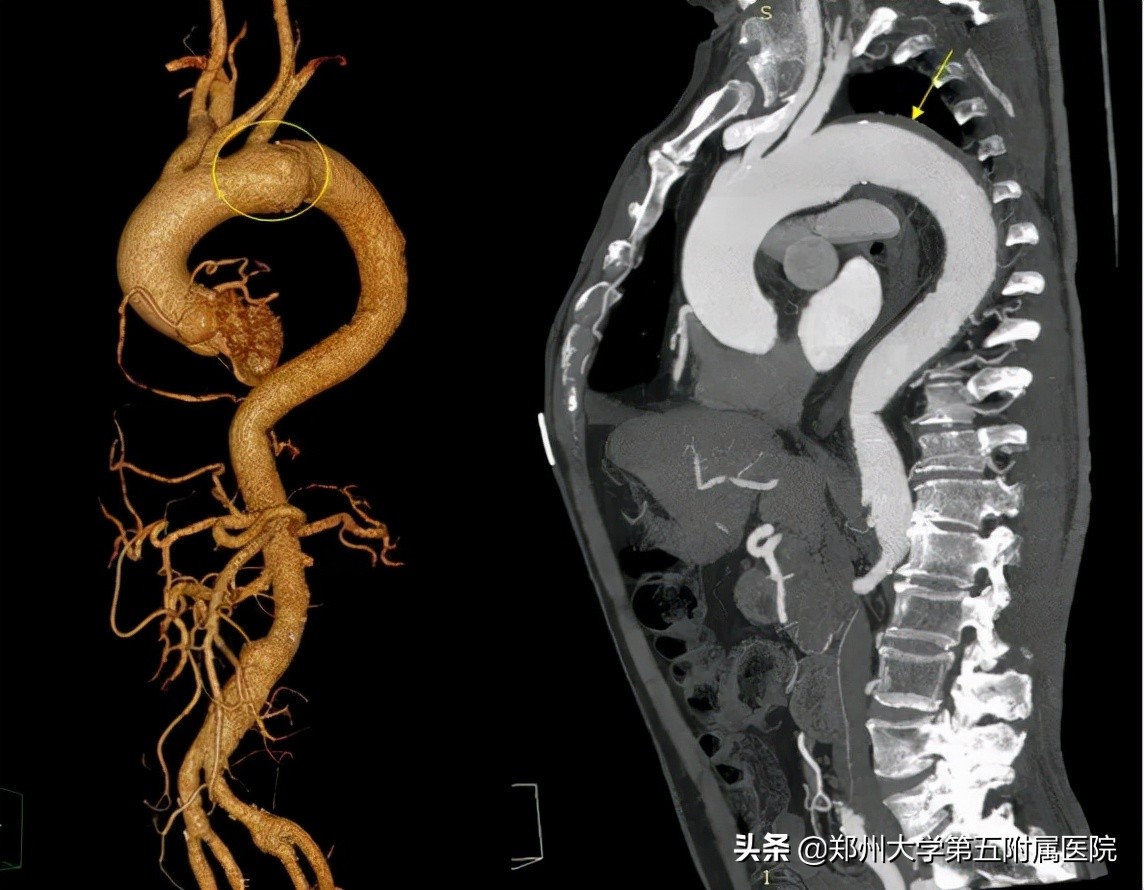

▲ 再次发病后,医院CTA提示主动脉弓部扩张(左),提示主动脉局部破口(中)(右)